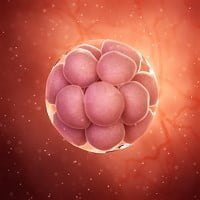

Döllenme ve implantasyondan sonra, bebeğiniz ilk 3 hafta boyunca sadece bir embriyodur: tüm organların ve vücut parçalarının gelişeceği iki hücre tabakasından oluşur. Bu erken aşamada, bebeğiniz hızla büyür ve kısa süre içinde barbunya büyüklüğüne ulaşır, sürekli hareket eder. Kalbi hızla atmaya başlar ve bağırsakları oluşur.

İmplantasyon (yerleşme) süreci, endometrium (rahim iç duvarı) içine yerleşen bölünmüş hücre yumağının (morula) hızla çoğalmasıyla başlar. Bu hücreler, bebeği oluşturacak yapıları geliştirmeye başlar ve gebelik hormonu olan hCG (insan koryonik gonadotropin) üretilmeye başlanır.